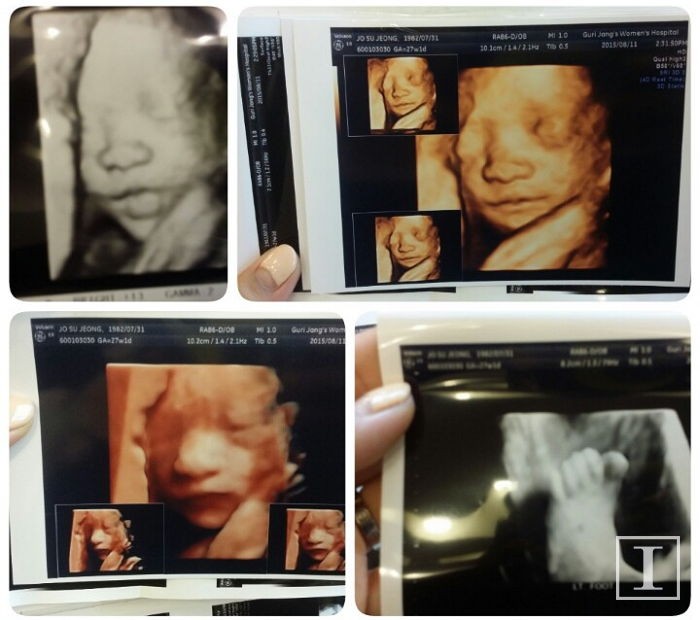

사진제공 = 제보자 A씨

2015년 2월 생애 첫 아기가 생긴 부부는 출산까지 10개월 동안 산부인과에서 정기검진을 꾸준히 받으며 아기가 하루라도 빨리 세상에 나오기만을 기다렸다.

하지만 출산 당일 아기는 태변(胎便)을 먹은 채 태어났고, 심장박동수는 미비했다. 그리고 태어난지 불과 6일 만에 아기는 세상을 떠나고 말았다.

A씨는 인사이트와의 인터뷰에서 "아기가 아내 뱃속에 있을 당시 몸무게가 2.5kg으로 건강했다"며 "아기가 태변을 먹었다는 건 그만큼 스트레스를 받았다는 증거"라고 말했다.